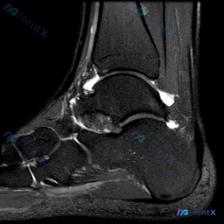

看到一份很有代表性的踝关节MRI影像,整理了资料和分析思路分享给大家。 病例影像基本信息 这是一份踝关节矢状位T2加权像(T2WI),先给大家说下客观观察到的结果: 1. 解剖结构显示清晰:可以看到胫骨远端、距骨、跟骨、足舟骨及部分跖骨 2. 核心异常发现: - 胫距关节腔前方、后方可见明显T2高信...